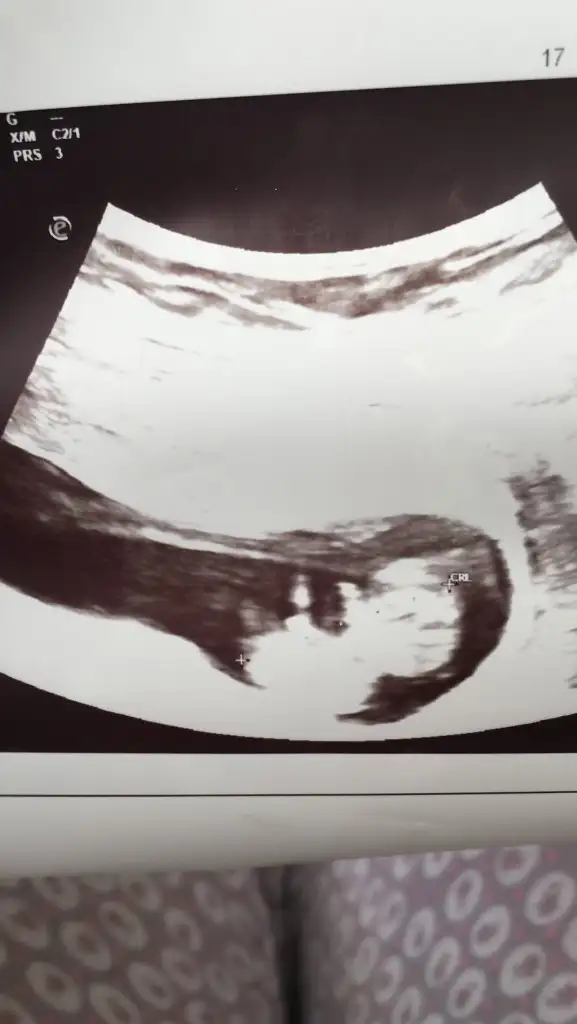

dr soylemeden siz gorun genital nub teorisi ( bebegin cinsiyeti)

Kızlar yorum istiyorum doktor daha küçük dedi 12 haftada ☺️☺️